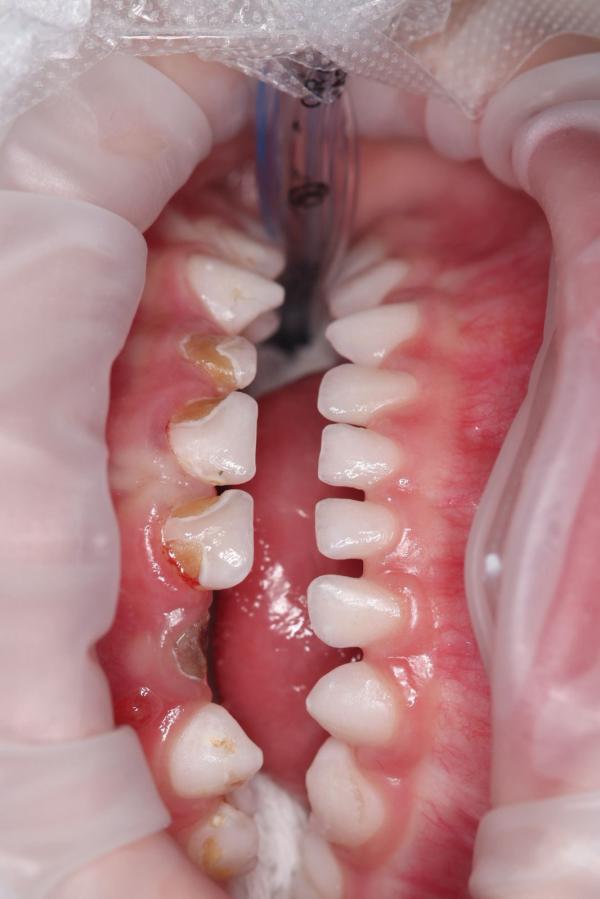

@madina_mansur, а нижний зуб отсутствовал, нарастили его?

@_saltanat_, нижние зубы у него здоровые. Только верхние лечили. Верхний зуб один раскрошился в марте. Его наростили. На 6 Зубов сделали коронки( передние 4 и жевательные 2 верхних